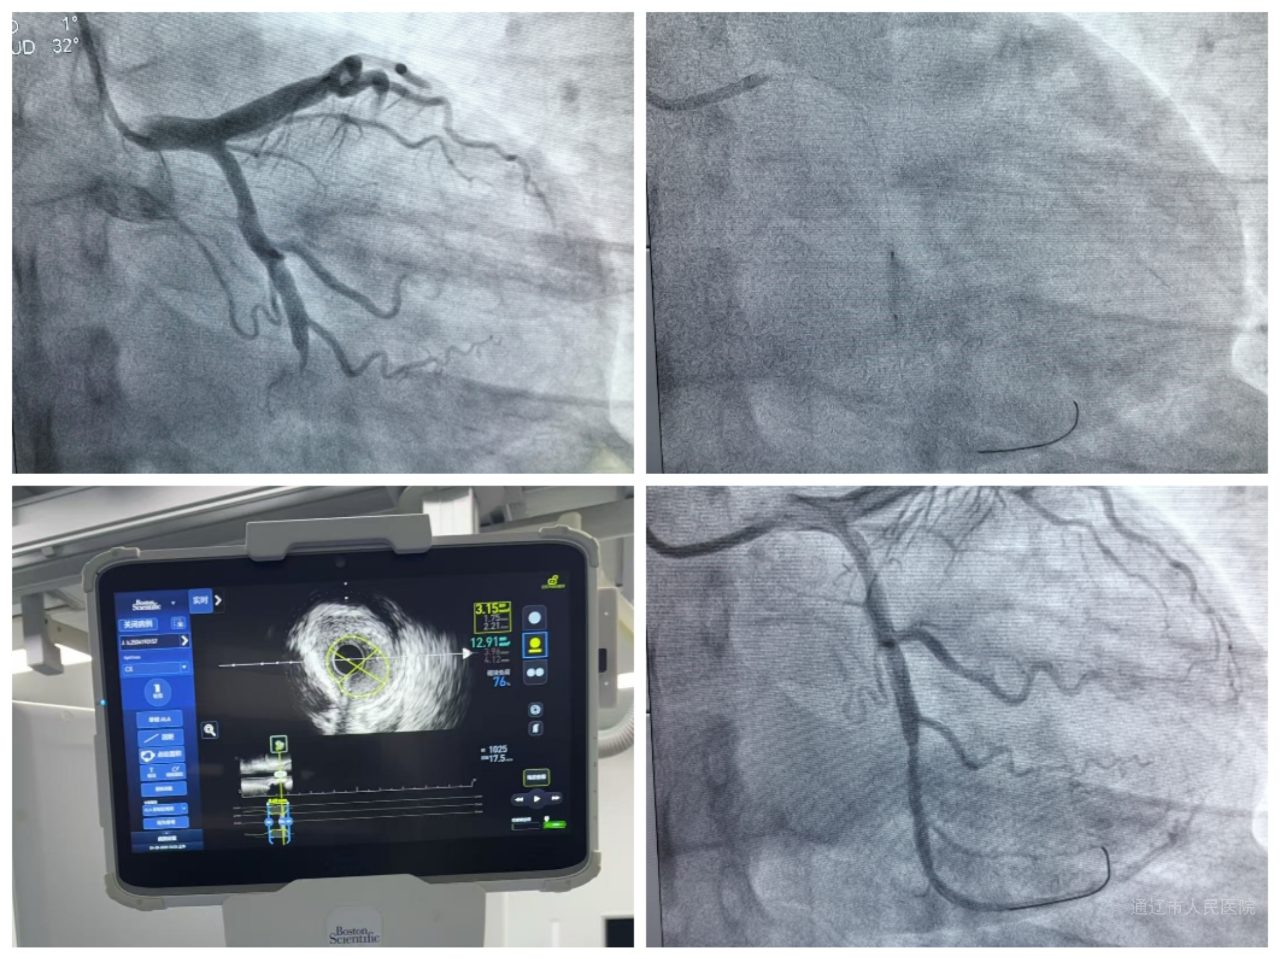

AVVIGO人工智能一体机集成血管内超声(IVUS)和血流储备分数(FFR/DFFR)两大核心技术,并深度融合人工智能算法,实现了诊疗技术的全面升级。IVUS技术能够提供360°超高清血管横断面图像,精准识别斑块性质、评估血管狭窄程度及病变长度,有效突破传统造影的局限性;FFR技术则可实时测定血管功能学指标,避免“过度治疗”或“治疗不足”的情况发生,让每一台手术都更具针对性;人工智能系统能够自动分析数据,辅助医生制定最佳治疗策略,大幅提升手术的精准度与安全性。

该设备投入使用后我院心血管内科团队已成功开展多例高难度手术。其中,一名27岁年轻冠心病患者在AVVIGO一体机的辅助下,顺利完成“无植入”介入治疗,通过药物球囊技术保留了血管自然结构,既避免了支架植入,又有效降低了医疗费用,实现了良好的治疗效果。

AVVIGO一体机的应用具有显著技术优势:通过IVUS+FFR双模态评估,实现从“经验医疗”向“数据驱动”的跨越;借助AI辅助制定个性化治疗方案,减少不必要的支架植入;药物球囊技术尤其适用于年轻患者、小血管病变及分叉病变等特殊病例;实时监测功能进一步保障手术安全,提升治疗成功率。